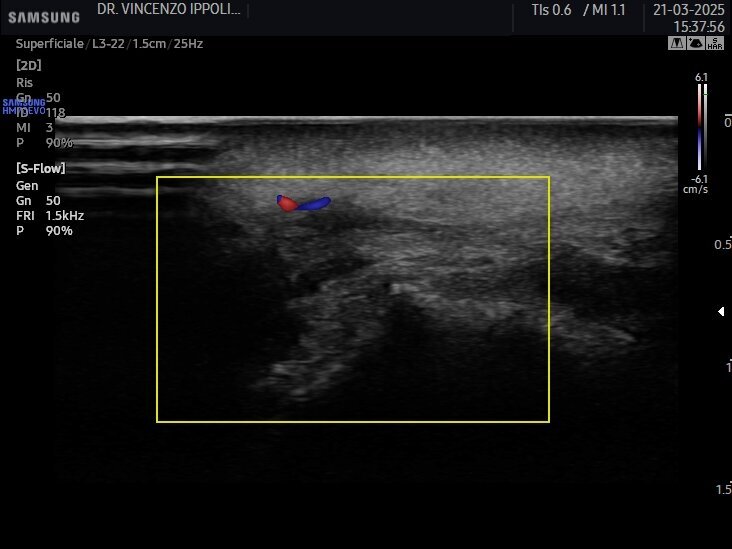

Gli ultrasuoni forniscono immagini in tempo reale con accuratezza variabile e dipendente dalle capacità dell’operatore e dalle potenzialità dell’apparecchiatura ecografica per uno studio accurato della cute e degli strati più superficiali del volto ma nascosti dall’epidermide (Fig. 1). Consentono una mappatura precisa delle strutture vascolari a prescindere dalle loro varianti anatomiche ed una valutazione della motilità dei piani muscolari. Ciò significa che con l’esame ecografico è possibile passare dall’osservazione anatomica statica a quella dinamica e valutare le straordinarie differenze ai fini diagnostici, esecutivi e post-operatori (Fig. 2) (clicca QUI e guarda il video). A causa della crescente popolarità delle procedure estetiche mininvasive al volto mediante tecniche iniettive/infiltrative/implantari, l’esame ecografico facciale è diventato fondamentale per tracciare i prodotti iniettabili, prevenire complicanze e, se necessario, riconoscerle per intervenire tempestivamente. Eventi avversi possono verificarsi al momento dell’iniezione, come le occlusioni o le compressioni vascolari, subito dopo il trattamento, come le infezioni, o diversi mesi dopo, come la comparsa di reazioni nodulari infiammatorie. Eseguire una metodica estetica al volto, sia essa infiltrazione di filler, iniezione intramuscolare di tossina botulinica o impianto di fili di trazione o di biostimolazione, sotto guida ecografica, fornisce un riscontro dinamico contestuale del posizionamento del riempitivo, consentendo al clinico di operare nell’area anatomica prescelta evitando sconfinamenti indesiderati (clicca QUI e guarda il video).

L’incidenza di complicanze vascolari dopo le iniezioni di filler pare essere 1/6600 (0,015%). Tuttavia, sebbene questo rischio non sembri molto elevato, anche un operatore esperto può incorrere in questo evento avverso. Se, da un lato, gli ultrasuoni possono aiutare nell’identificare e valutare il decorso dei vasi sanguigni a rischio di occlusione o compressione (Fig. 3), dall’altro, in caso di evento avverso correlato al filler a base di acido ialuronico, l’enzima ialuronidasi può essere iniettato con la guida degli ultrasuoni esattamente nel deposito del prodotto per una sua mirata dissoluzione (Fig. 4). Con l’avanzare dell’età, l’immagine della cute si modifica sia negli spessori sia nel numero degli annessi. L’esame ecografico contribuisce a visualizzare il progressivo deterioramento cutaneo: un assottigliamento del derma, la riduzione delle fibre collagene, la degenerazione delle fibre di elastina e la disidratazione influiscono sull’ecogenicità dei tessuti esaminati (Fig. 5).

la mappatura dei vasi della zona oggetto di intervento (Fig. 7 - clicca QUI e guarda il video; Fig. 8 - clicca QUI e guarda il video; Fig. 9 - clicca QUI e guarda il video);